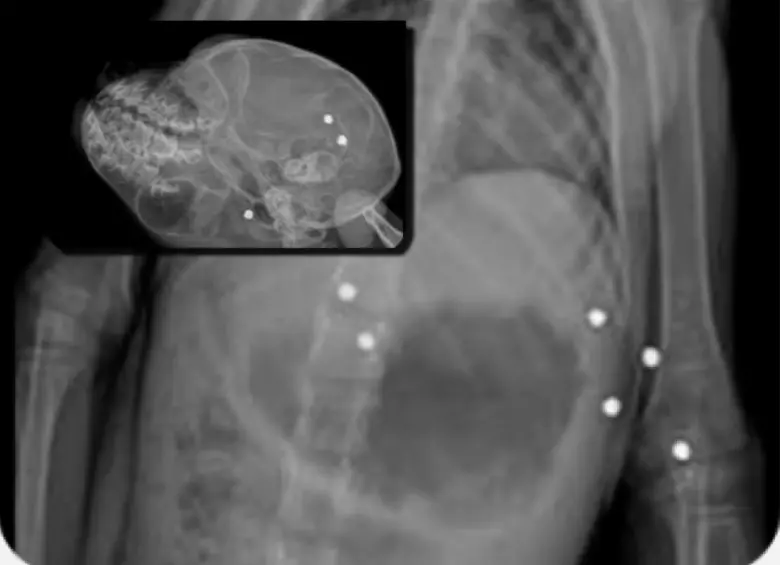

• En el cuerpo del primate, habían 19 perdigones alojados en distintas partes de su cuerpo. FOTO: Corantioquia

En el cuerpo del primate, habían 19 perdigones alojados en distintas partes de su cuerpo. FOTO: Corantioquia

El médico veterinario Andrés Rodríguez, quien lo atendió, explicó que la radiografía mostró 19 perdigones de aproximadamente tres milímetros de diámetro —casi el grosor de una moneda de 1.000 pesos—, alojados en el cráneo, las extremidades y el tórax. Las heridas comprometieron su movilidad de forma irreversible e impidieron su regreso al hábitat natural. Con el paso de los días, las lesiones se agravaron hasta causarle la muerte.